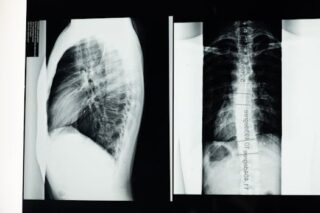

Endplate osteophytes are typically identified through imaging studies such as X-rays, CT scans, or MRIs. These scans can provide a clear picture of the spine’s structure and reveal the presence of any osteophytes. Diagnosis often occurs when investigating other spinal conditions or symptoms. For accurate assessment, healthcare professionals consider a patient’s history, symptoms, and physical examination findings alongside imaging results.